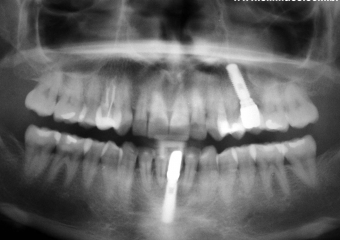

Imagens do elemento 31, apresentando extensa reabsorção radicular externa

Imagens finais do caso terminado em fevereiro de 2010, com prótese em porcelana sobre implante